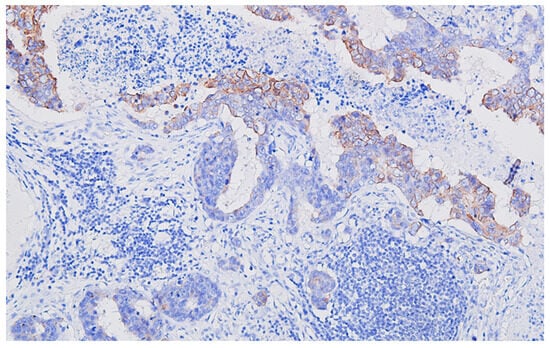

Collision Tumors of the Colon and Peritoneum: Signet-Ring Cell Carcinoma and Granular Cell Tumor

2. Case Report

Histopathological Findings